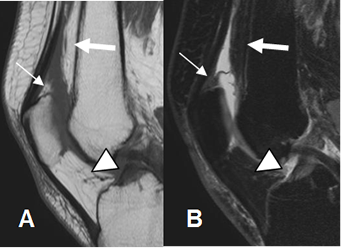

El cartílago articular es una estructura de bordes regulares y señal de intensidad (SI) homogénea, hipo o hiperintensa, según la secuencia elegida. (13). Las secuencias en T1 tienen buena sensibilidad para detectar lesiones condrales. (14).

Utilizando secuencias en T1 FS 3D FLASH, el cartílago muestra un aspecto trilaminar, con regiones superficial y profunda delgadas e hiperintensas y otra región media de señal intermedia. (15). (Fig 34 y 35).

Fig 34. Cartílago articular normal.

RM sagital en T1. Cartílago normal con señal intermedia y homogénea.

Fig 35. Cartílago patelar normal.

A: RM axial en T2. Cartílago normal, con señal homogénea e hipointensa.

B: RM axial 3D en T1 STIR. Cartílago hiperintenso y de aspecto trilaminar.